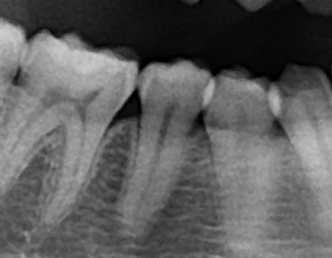

A.画像を見たらわかる通り、歯と歯の間には隙間があります。

また、画像を見てもらったらわかると思いますが、歯はくびれています。

実際に糸ようじで隙間の部分を綺麗にしようとしても中々くびれの部分まで綺麗にするのは困難です。

よってより効果的に汚れを取るために歯間ブラシは効果的だと考えられます。

虫歯、歯周病予防を考える上で歯間ブラシはなくてはならない存在です。]]>